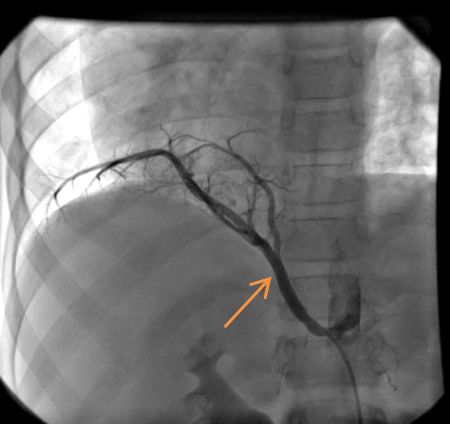

Routine laboratory analysis, including a complete blood count and metabolic panel, is normal. A postero-anterior chest roentgenogram is shown in Figure 1. Chest computed tomography (CT) without IV contrast (Figure 2), and gadolinium enhanced magnetic resonance angiogram (Figures 3 and 4) are also obtained. A decision is made to perform a cardiac catheterization (Figures 5 and 6) for further evaluation.

Figure 4

A cardiac catheterization is performed. Right pulmonary artery and descending aorta injections (Figures 11 and 12) show a large scimitar vein and aortopulmonary collaterals to the right lung (orange arrow, Video 2). Coil occlusion of the aortopulmonary collateral is done at the time of the cardiac catheterization. Qp:Qs was 1.3:1 on both MRI and on cardiac catheterization.